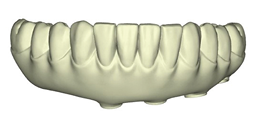

These new records along with the Nexus scans taken at the time of implant surgery were sent to Osteon Medical through the Nexus iOS portal with instructions to replicate the provisional restoration design with correct adaptation to the healed soft tissue. Three days after the data was submitted to Osteon Medical, .STL files of the final design for the maxillary and mandibular restorations were sent through the portal to our office and 3D printed in our office (Figs. 23A-C).

Fig. 23A

Fig. 23B

Fig. 23C